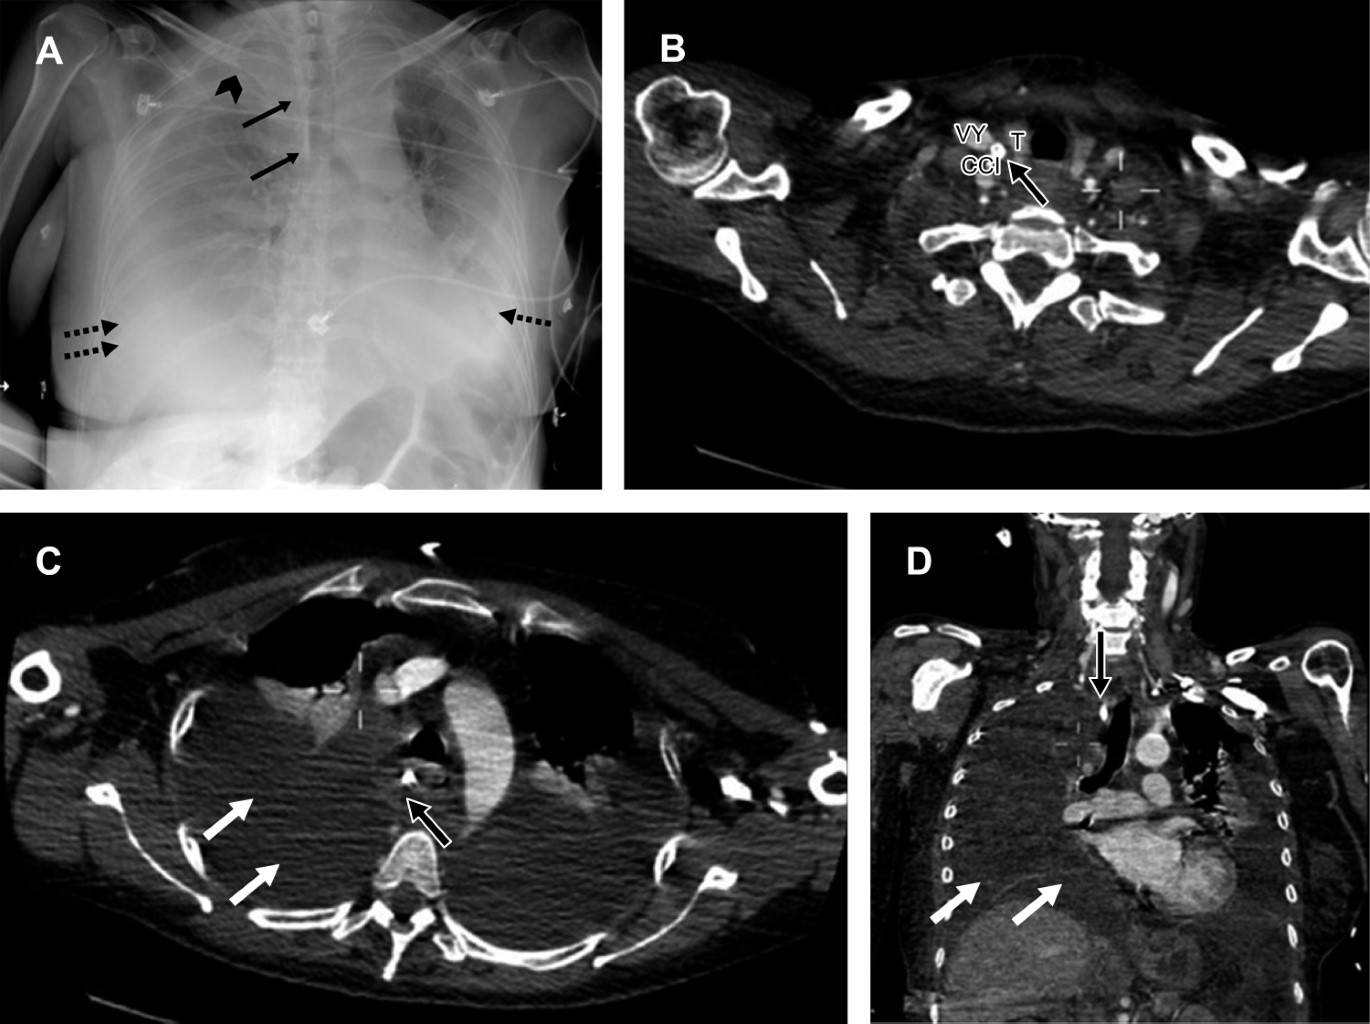

• 2. Laceración traqueobronquial. La laceración traqueobronquial secundaria a la intubación endotraqueal no es común, se documenta en aproximadamente una de cada 20,000 a 75,000 intubaciones.14 La muerte ocurre en 30% de los pacientes con este tipo de complicación, y 50% de estos casos se da en las primeras dos horas.5

En cuanto a la anatomía, destacamos que la pared posterior de la tráquea es membranosa predisponiéndola al trauma, cuando la lesión se asocia al dispositivo endotraqueal el sitio de lesión más común es éste. Los hallazgos radiológicos incluyen neumotórax bilateral, enfisema subcutáneo masivo (si la lesión involucra la hipofaringe el aire se extiende y diseca la región cervical)1 y neumomediastino (Figura 2).8,14,15

Existen algunas imágenes en relación al dispositivo que nos permiten sospechar una ruptura traqueobronquial como la disposición oblicua del tubo con desviación hacia la derecha, y sobredistensión del globo con un diámetro anteroposterior mayor de 2.5 cm.8,15

Cuando el defecto es significativo y coincide con el nivel de la laceración, el globo mostrará herniación adquiriendo una configuración "en reloj de arena" (ocasionalmente se presenta como complicación de la traqueostomía);14 esto se puede identificar en la tomografía computarizada hasta en 70 y 100% de los casos.16

Por lo regular el sitio puntual de la lesión es sutil, siendo complicado o muchas veces imposible de localizar por medio de los estudios de imagen. Debido a esto, es importante recordar que la membrana posterior de la tráquea es más vulnerable al trauma directo en comparación con los anillos cartilaginosos anteriores, por lo que realizar la búsqueda de la lesión en esta topografía es una recomendación útil.14